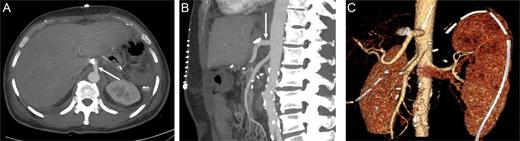

At this point, the patient was recommended for further investigation in the Interventional Radiological Department for both diagnosis confirmation and, most importantly, to provide an opportunity for stenting the celiac trunk. In order to accomplish this, gastro-duodenostomy, choledoco-choledocostomy (anastomosis between the resected common bile duct) and jejuno-jejunostomy re-anastomosis were performed, and a temporary abdominal closure was done. The patient was taken to the Radiological Department. CT and angiography (Figs 2 and 3) showed that there was a narrowing part of the celiac trunk, and distal to this part, there was an occlusion (high degree of stenosis) of the celiac artery. In addition, retrograde filling of the GDA could be appreciated through the patent SMA (Fig. 3). A stent was considered impossible due to the high degree of stenosis that was a nearly total occlusion of the celiac trunk.

Contrast-enhanced CT in the arterial phase: axial (A) and sagittal (B) maximum intensity projections (MIP), and coronal oblique 3D volume-rendered (VR) images (C) demonstrating proximal celiac artery narrowing (arrow) due to compression by the median arcuate ligament. Downstream, an additional high-degree stenosis of the celiac trunk can be appreciated (dashed arrow).

Digital subtraction angiography (DSA) with pigtail catheter placed in the abdominal aorta: coronal (A) and 70° left anterior oblique (LAO) projections (B) demonstrating complete occlusion of the celiac trunk (dashed arrow). In addition, retrograde filling of the GDA can be appreciated through the patent SMA. RHA, right hepatic artery; LHA, left artery.